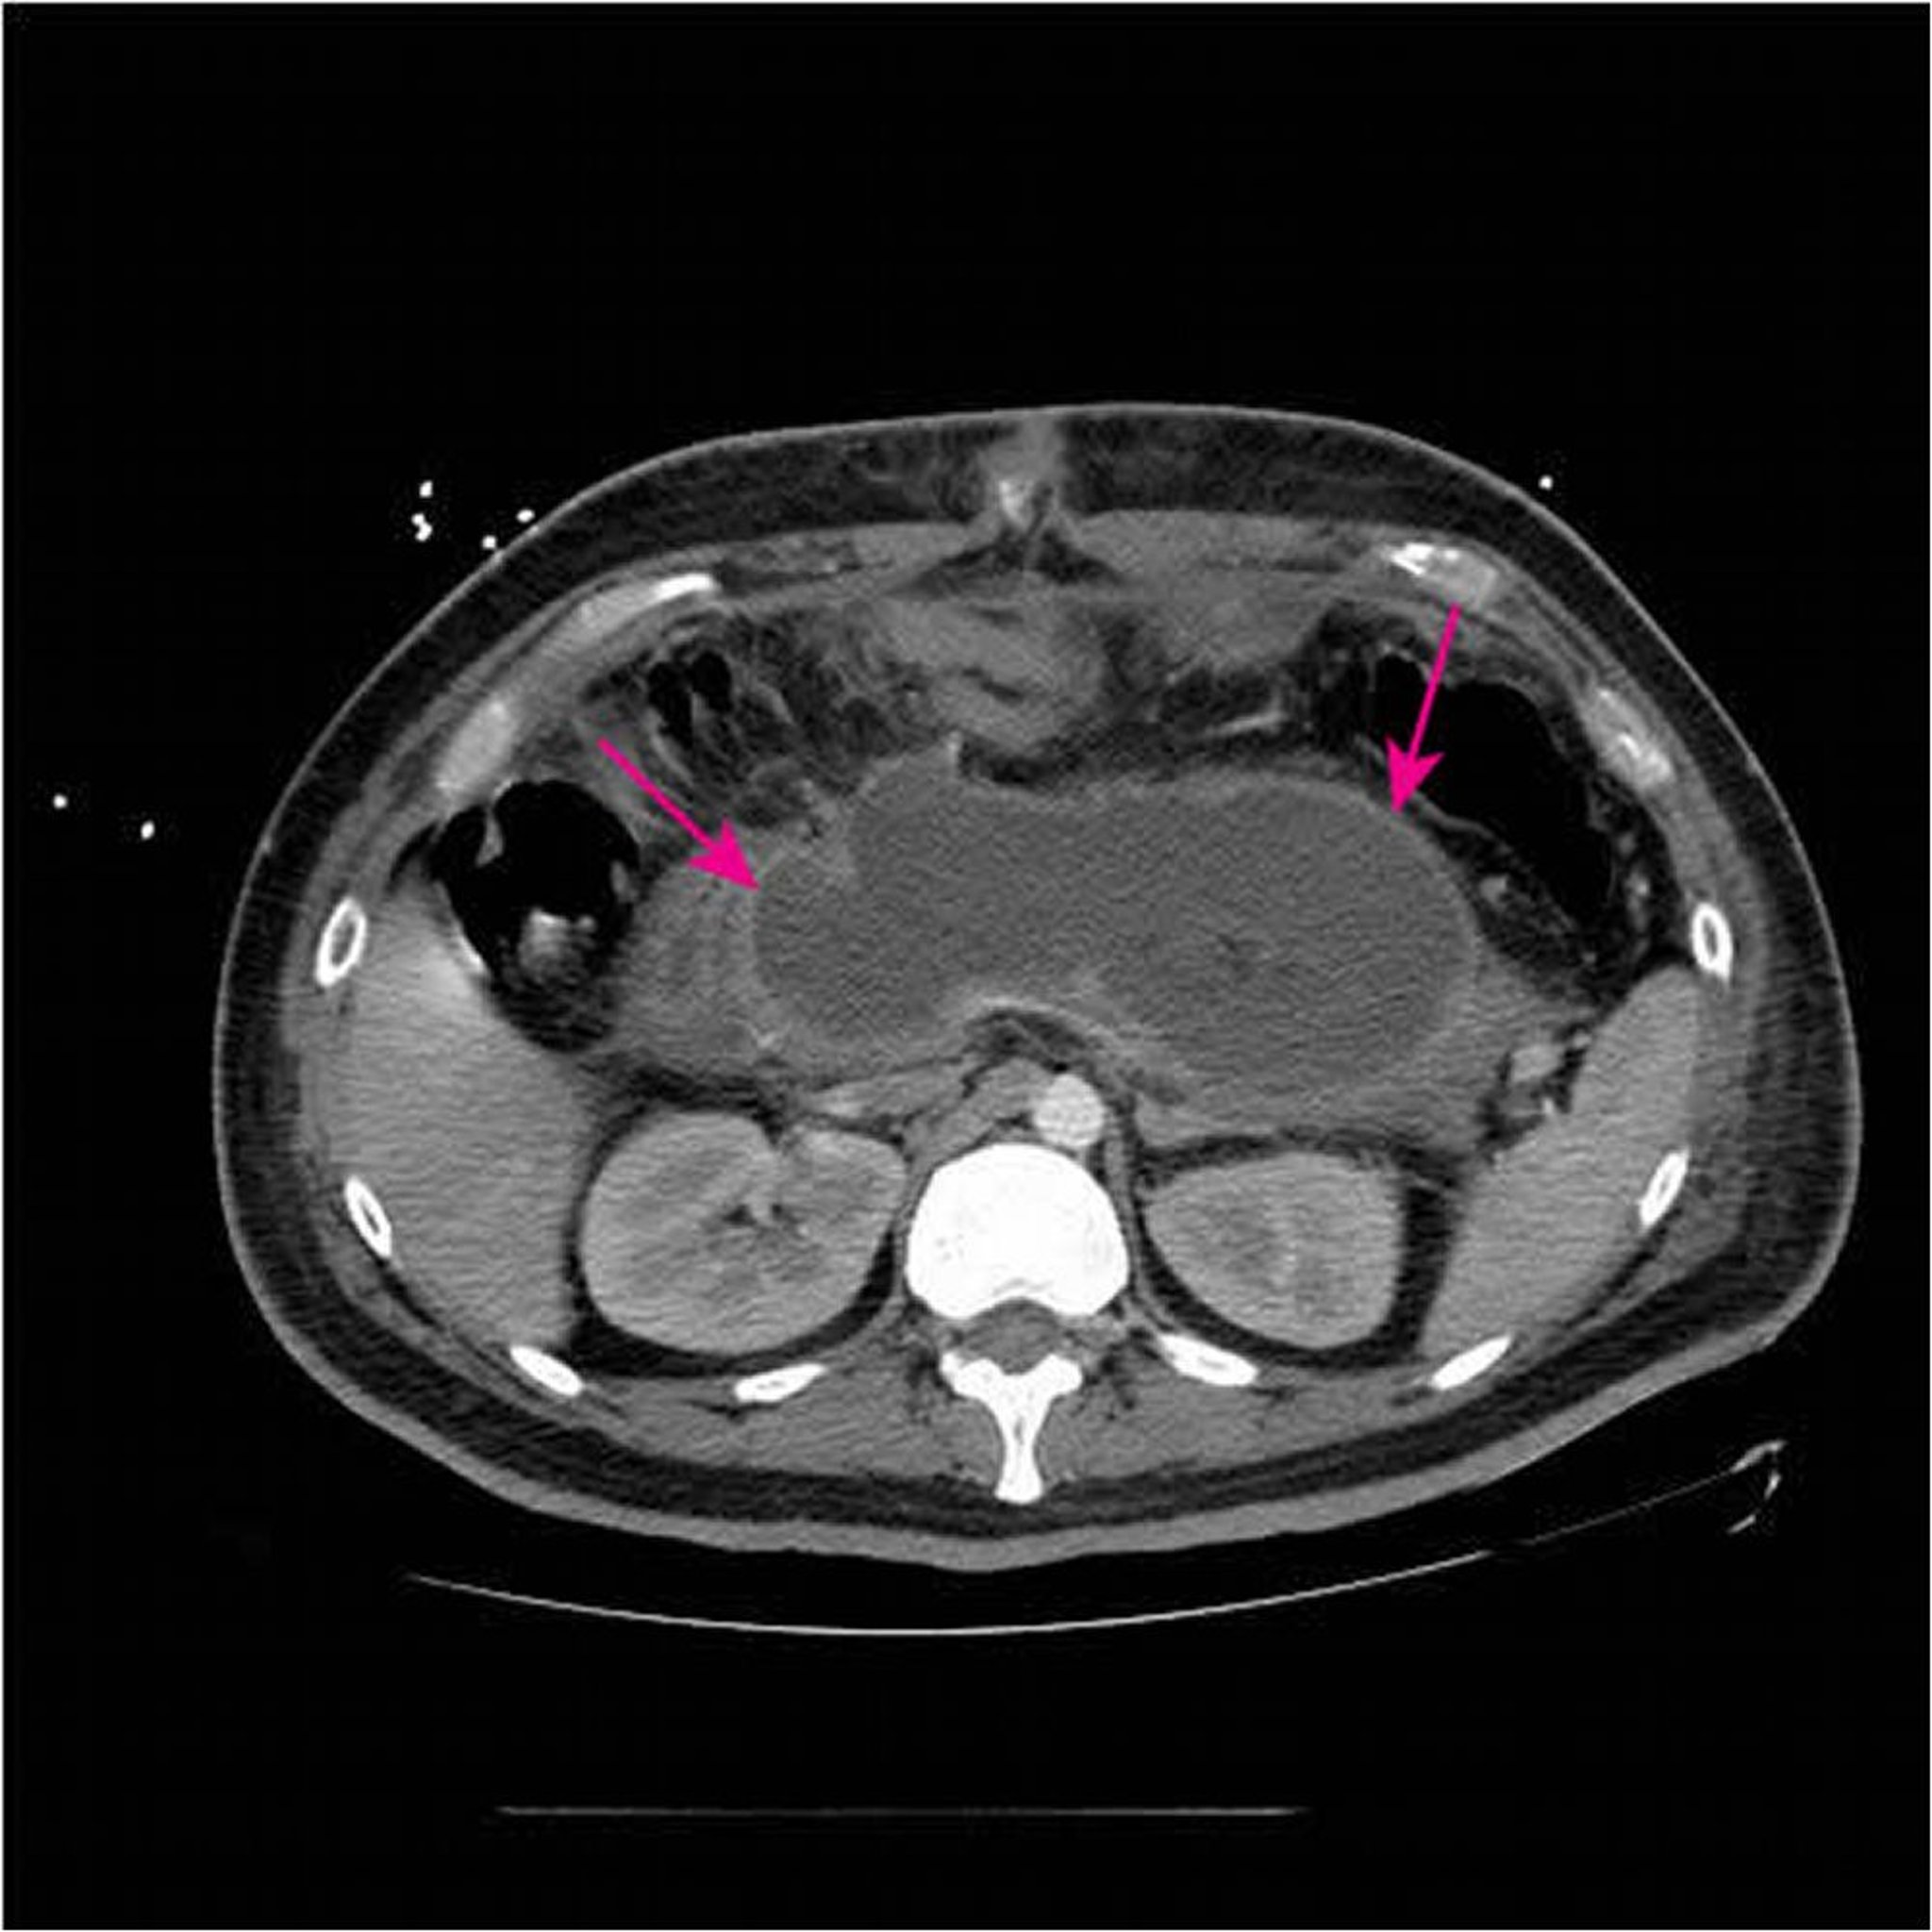

Acute necrotizing collection

静注および経口造影剤を使用したこのCT像では,壊死性膵炎の発症後4週間未満で膵組織の大部分が大きなacute necrotizing collection(矢印)に置換されたことが示されている。

Image courtesy of Sonam Rosberger, MD.